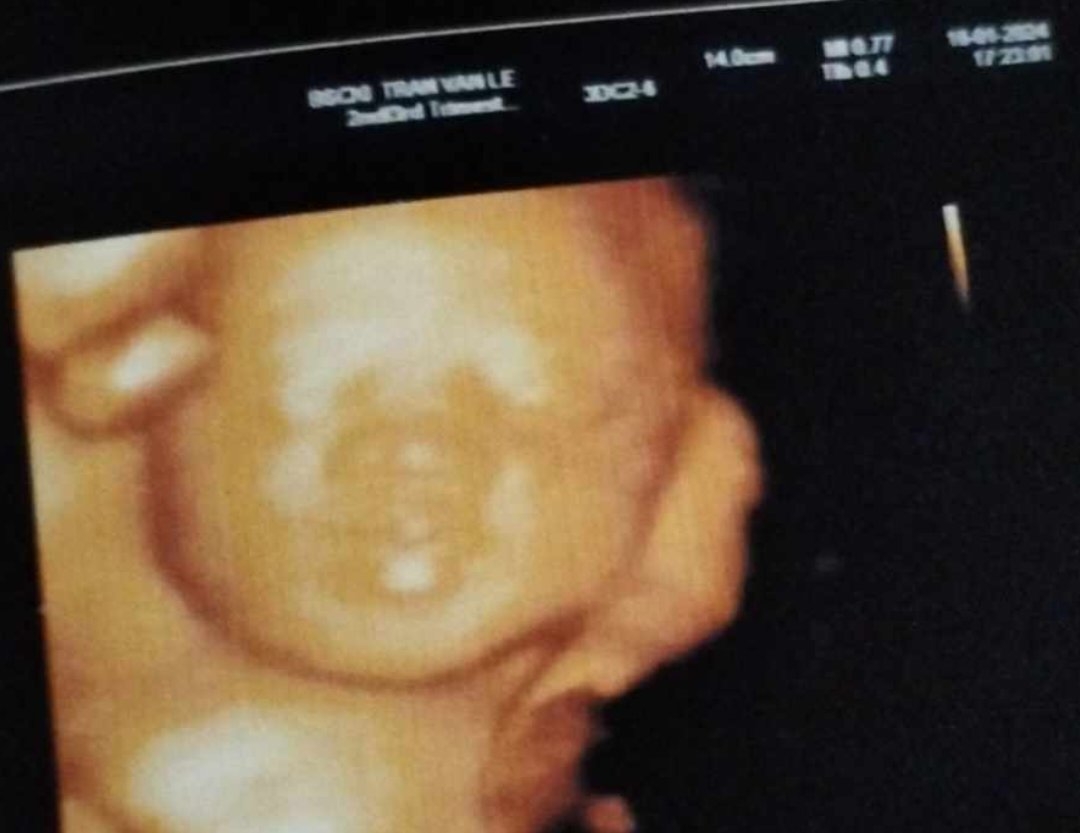

Lion 29w